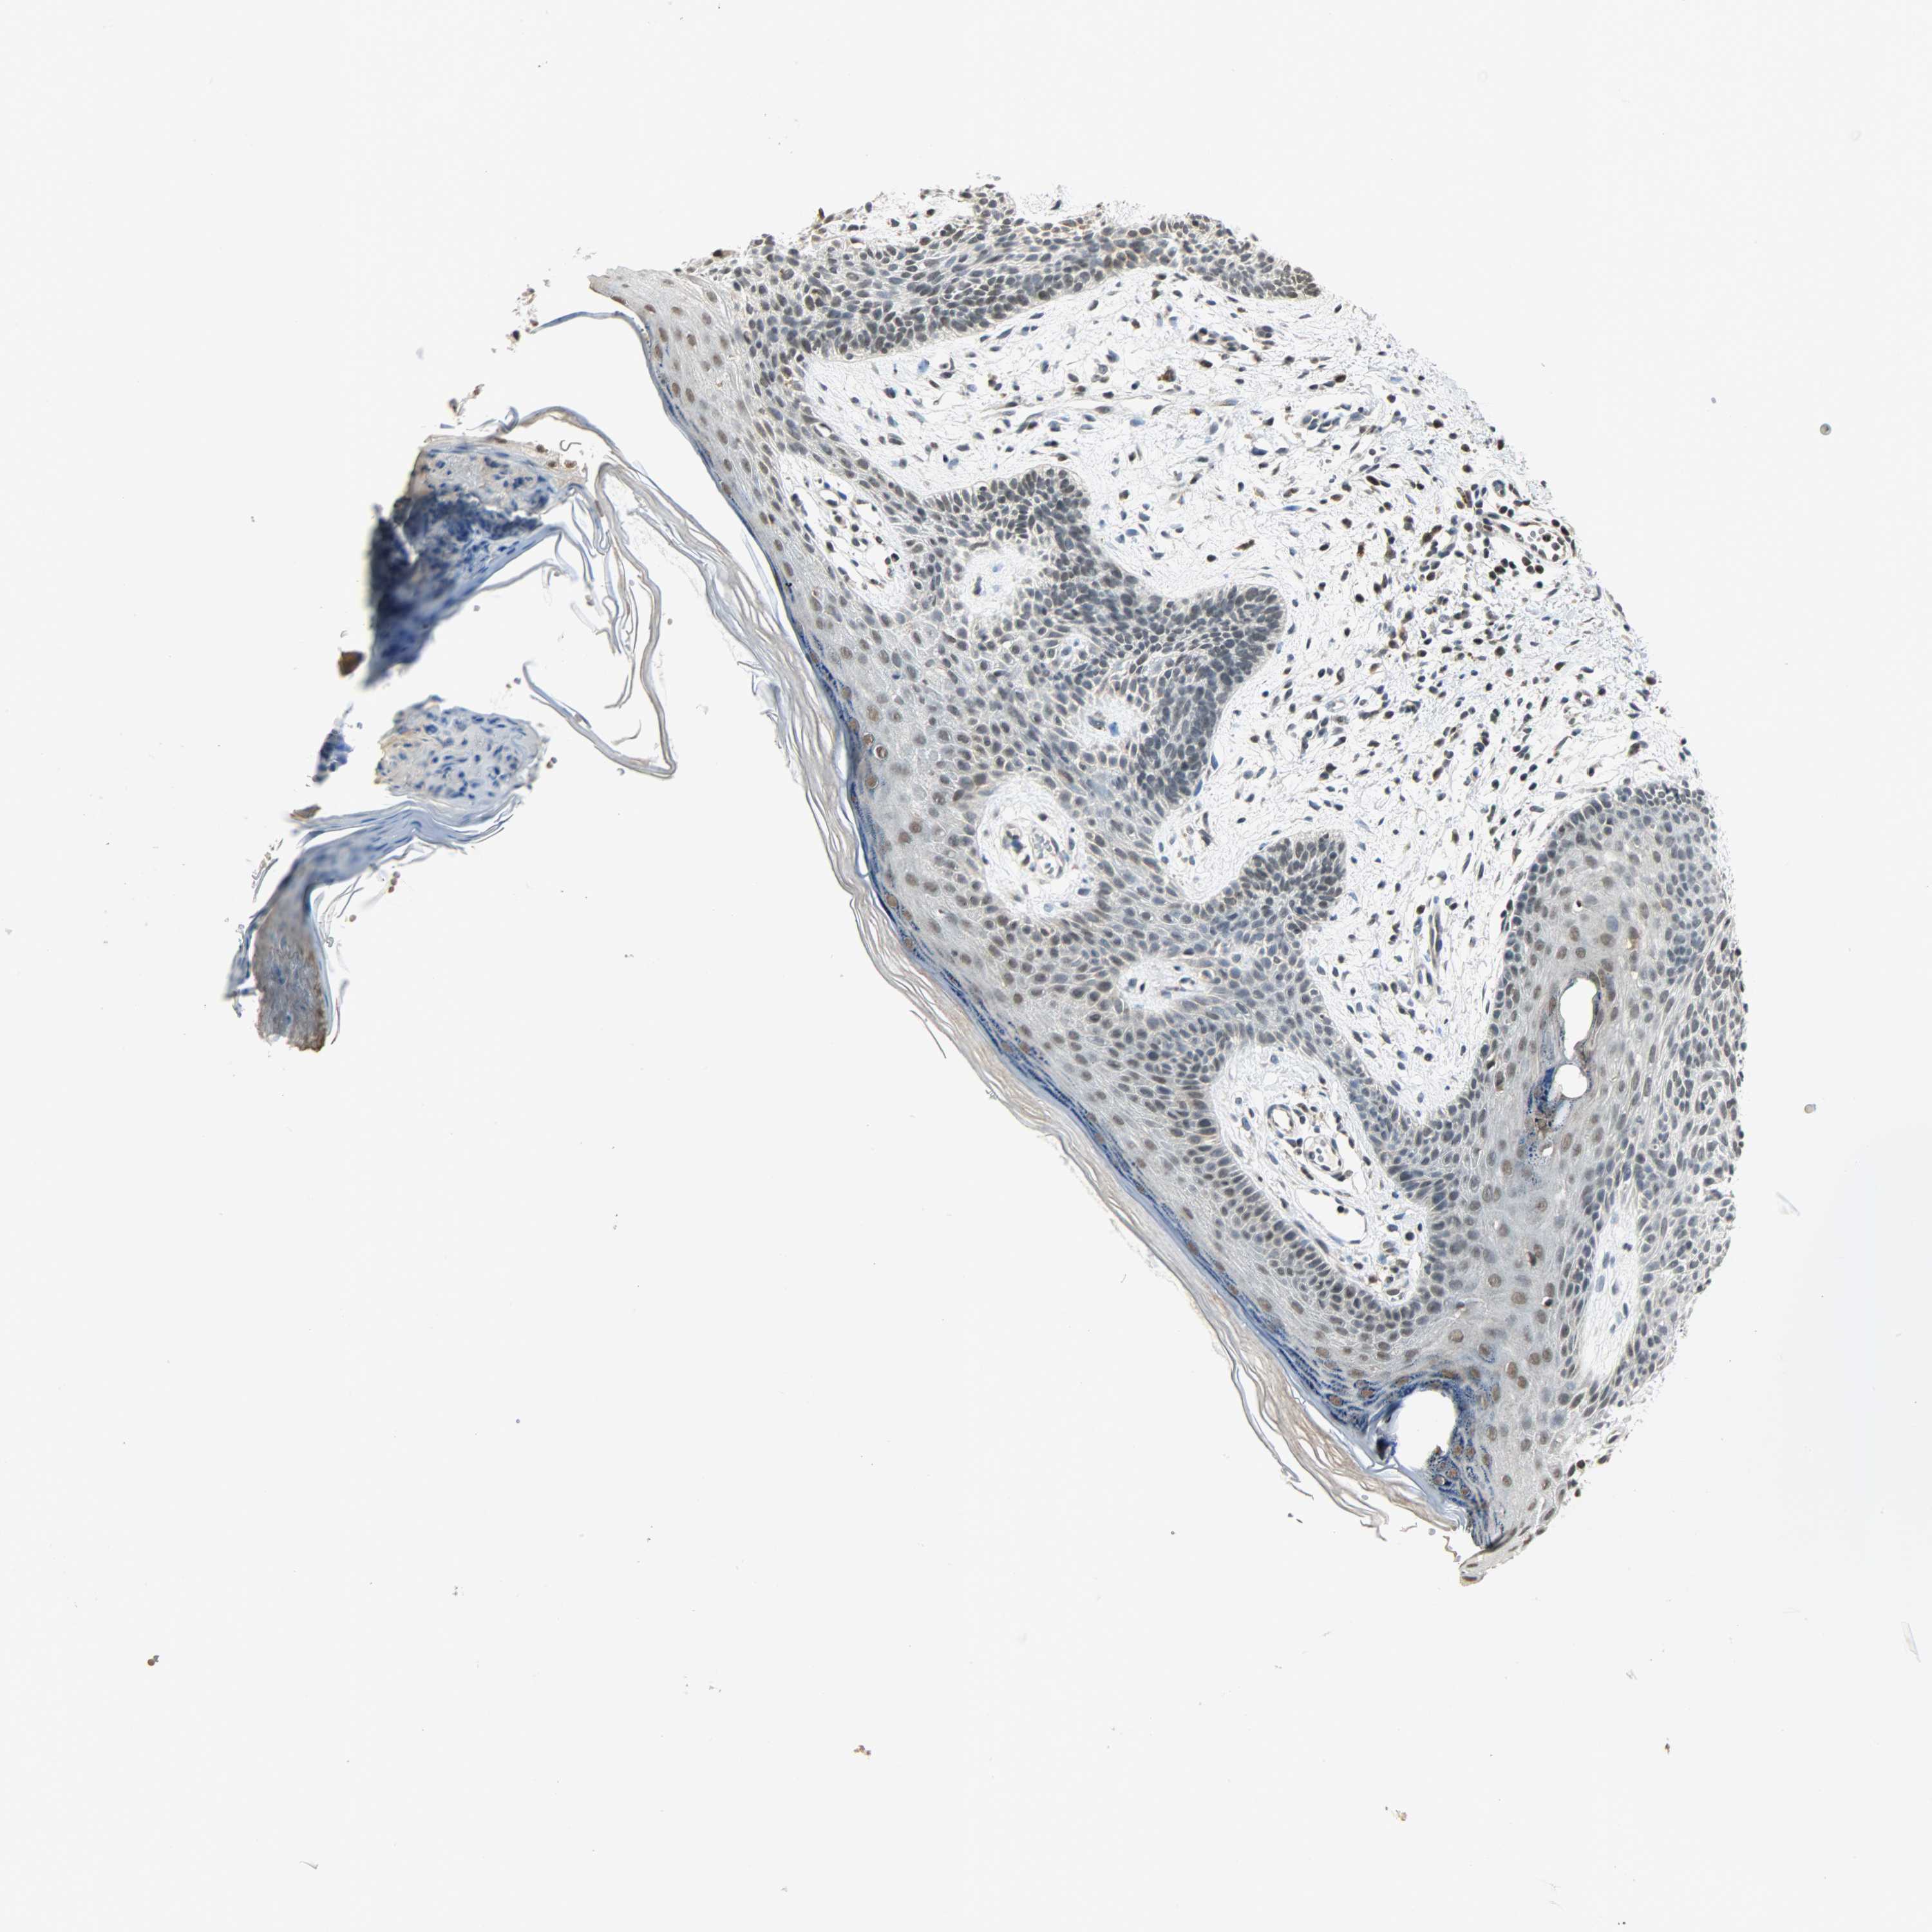

SKIN CANCER - Protein expressioni

A mouse-over function shows sample information and annotation data. Click on an image to view it in a full screen mode. Samples can be filtered based on level of antibody staining by selecting one or several of the following categories: high, medium, low and not detected. The assay and annotation is described here.

Antibody stainingi

Antibody staining in the annotated cell types in the current human tissue is reported as not detected, low, medium, or high, based on conventional immunohistochemistry profiling in selected tissues. This score is based on the combination of the staining intensity and fraction of stained cells.

Each image is clickable and will lead to virtual microscopy that enables deeper exploration of all samples and also displays staining intensity scores, fraction scores and subcellular localization as well as patient and tissue information for each sample.

Antibody HPA008751

Antibody CAB005227

Staining

High

Medium

Intensity

Strong

Moderate

Quantity

>75%

75%-25%

Location

Nuclear

Cytoplasmic/membranous

Cytoplasmic/membranous,nuclear

Squamous cell carcinoma, NOS

Squamous cell carcinoma, metastatic, NOS

Basal cell carcinoma